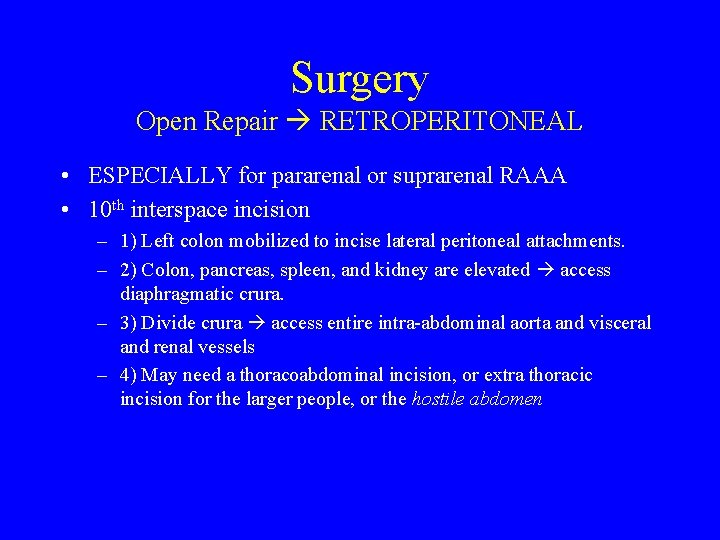

Surgery Open Repair RETROPERITONEAL • ESPECIALLY for pararenal or suprarenal RAAA • 10 th interspace incision – 1) Left colon mobilized to incise lateral peritoneal attachments. – 2) Colon, pancreas, spleen, and kidney are elevated access diaphragmatic crura. – 3) Divide crura access entire intra-abdominal aorta and visceral and renal vessels – 4) May need a thoracoabdominal incision, or extra thoracic incision for the larger people, or the hostile abdomen